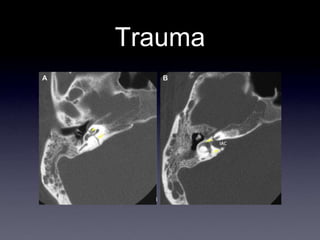

Trauma